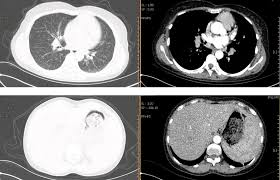

医生不会凭一句“多发结节”就吓你,而是综合以下 5 个特征👇:

🩺 医生解读:

“多数 3–5mm 小结节都是良性的炎症残影。真正需要关注的,是那些‘单侧、毛刺状、在短期复查中长大的’结节。”

现代高分辨 CT(HRCT)的分辨率极高,能看到0.2mm的结构,